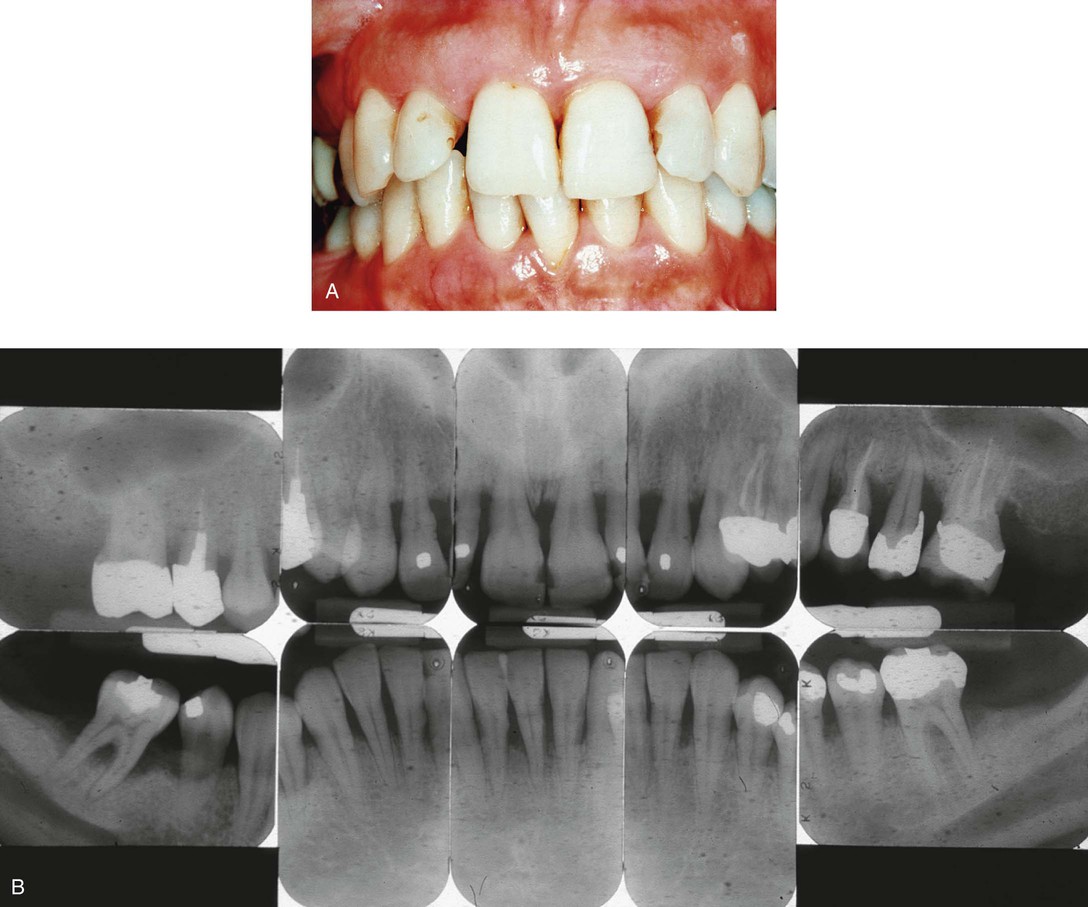

Gingivitis is found only in the epithelium and in gingival connective tissues. No tissue recession or loss of connective tissue or bone is associated with gingivitis (Fig. 14-4). Other types of gingivitis are associated with puberty, pregnancy, and the use of birth control medications (Box 14-2 and Fig. 14-5). Orthodontic appliances tend to retain bacterial plaque and food debris, resulting in gingivitis (Fig. 14-6). Instruction regarding proper home care is a critical part of orthodontic treatment (see Chapter 60).

Periodontitis is inflammation of the supporting tissues of the teeth. The inflammatory process progresses from the gingiva into the connective tissue and alveolar bone that support the teeth (Fig. 14-7). The connective tissue attachment at the base of a periodontal pocket is destroyed as the disease progresses.

Periodontal disease is described in terms of disease severity and how much of the mouth is affected:

• If more than 30% of sites in the mouth are affected, the disease is considered generalized (Fig. 14-8)